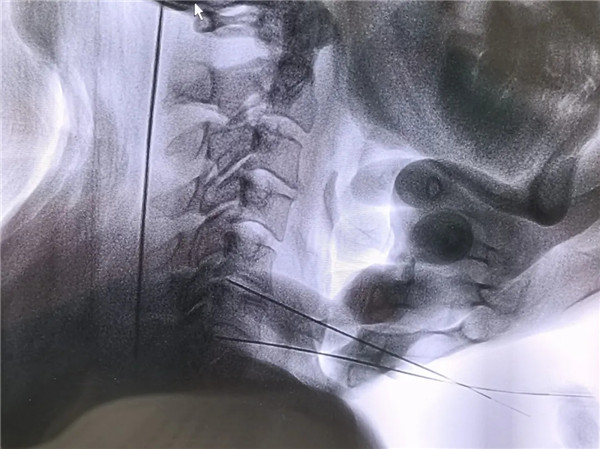

2年前,劉師傅出現左側肩背部疼痛,反復發作,影響正常生活,多次嘗試理療、藥物治療,疼痛未能緩解。經多方打聽,來我院骨四科就診。結合臨床表現及相關檢查,考慮到劉師傅的病情和對微創治療的需求,骨四科主任楊永輝帶領團隊經過充分討論,決定為其實施:頸椎間盤射頻消融、膠原酶溶解術。手術采用局部麻醉,僅通過一枚穿刺針,成功實施射頻消融、膠原酶溶解術,術口僅針眼大小。手術過程劉師傅一直清醒:“沒想到這么快就做完了!也不痛,效果蠻好!”術后第一天查房,左頸肩部疼痛明顯緩解,劉師傅連聲感謝:“現在寶雞市人民醫院的技術太好了,不用開刀也能解決頸椎間盤突出的問題!”

頸椎間盤微創射頻消融聯合膠原酶溶解術是頸椎間盤突出癥的一種微創聯合治療方式,通過兩種技術的協同作用達到更好的治療效果。射頻消融先快速收縮部分突出組織,為膠原酶創造有利的作用環境;膠原酶進一步溶解椎間盤內的膠原蛋白,鞏固和增強減壓效果,形成“1+1>2”的協同作用,相比單一技術更能有效緩解頸肩痛、上肢麻木等癥狀。

1.創傷小:手術通過穿刺完成,僅留下針眼大小的創口,無需開刀,避免了開放手術對氣管、食道、血管、肌肉的剝離和牽拉,對周圍組織損傷極小,術后恢復快,感染風險低。

2.安全性高:在局部麻醉下進行,患者術中意識清醒,可及時反饋感受,醫生能更精準地操作,減少對神經、血管等重要結構的誤傷。

3.療效確切:兩種技術協同作用,射頻消融通過熱凝收縮突出組織,膠原酶特異性溶解椎間盤內膠原蛋白,雙重作用下能有效減輕椎間盤對神經根的壓迫,緩解疼痛等癥狀,多數患者術后癥狀可明顯改善。